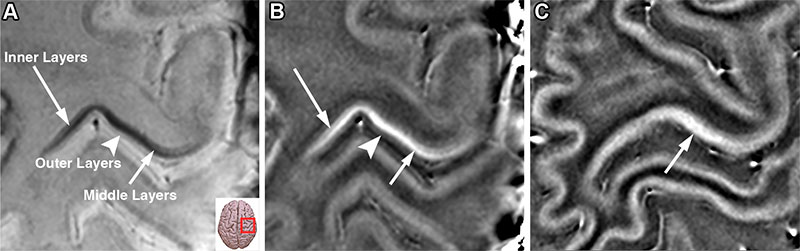

Integrating 4D Flow MRI into Clinical Practice

While conventional 2D flow MRI measures the unidirectional flow of blood through a predetermined imaging plane, 4D flow MRI captures blood flow velocity and volume in all three spatial directions over time. This enables a retrospective analysis of blood flow without needing multiple acquisitions.

A recent Radiology review highlighted the potential of 4D flow MRI as a valuable tool across a wide range of cardiac MRI applications.

Gert Reiter, PhD, and Clemens Reiter, MD, both from the Department of Radiology at the Medical University of Graz in Austria, and colleagues note that integrating 4D flow MRI into clinical practice offers significant benefits for diagnosis, disease monitoring and patient outcomes.

The authors found that 4D flow MRI surpassed 2D flow MRI in clinical workflow effectiveness by providing multiple measurements without requiring additional scan time and planning. With scan times of 10 minutes or less, 4D flow MRI improved workflow efficiency while also ensuring that all velocity, flow rate and volume measurements were from the same physiological state of the patients.

“Current research is increasingly focused on standardizing acquisition and postprocessing techniques for novel 4D flow–derived diagnostic and prognostic markers, including flow energetics, flow pattern analysis and vessel wall interaction,” the authors conclude.

Read the full article, “Four-dimensional Flow MRI for a Dynamic Perspective on the Heart and Adjacent Great Vessels.”

Four-dimensional flow MRI–derived left ventricular flow components. (A) Schematic drawing of the definition and color-coding of four left ventricular flow components. Dots indicate starting region, and arrows indicate movement during one cardiac cycle. (B, C) Determination of the left ventricular flow components for (B) a healthy control and (C) a patient with dilated cardiomyopathy (DCM) with reduced left ventricular ejection fraction. Four-dimensional flow MRI scans with color-coded particle traces at end systole (left) and end diastole (middle) are shown, together with the percentages of the flow components with respect to end-diastolic volume (pie chart). Note the differences in direct flow and residual volume components. See also Movies 16 and 17. AV = aortic valve, MV = mitral valve.